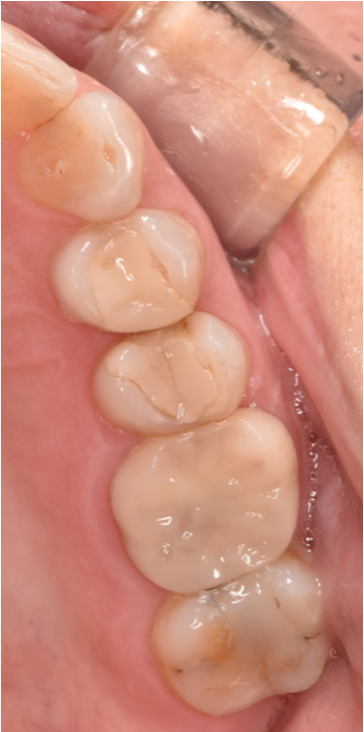

セラミック 2023.0240代女性「保険の銀歯を白くしたい」目立っていた金属の詰め物を外し、透明感と強度のあるセラミック「E-maxアンレー」で見た目も美しく修復した症例